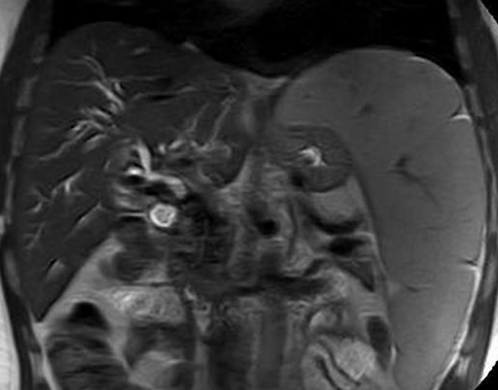

- Sur thrombose porte chronique ++

- Voie de dérivation Porto-Porte (contrairement à porto-systémique du reste de l’hypertension portale)

- Péri-veine porte et Lit vésiculaire ++

- Le Cavernome se développera surtout sur un foie sain avec occlusion porte rapide

Biliopathie portale

- La dilatation des petites veinules péri-biliaires peut compresser les voies biliaires (sorte de Mirizzi) → Biliopathie portale = dilatation souvent asymptomatique des VB